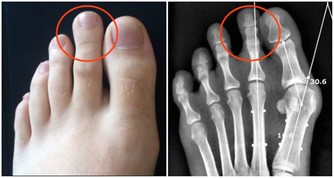

而當腫瘤生長,肝臟體積越來越大時,腫大的肝臟就會對膈肌造成一定的刺激,

從而導致膈肌出現痙攣,以致引起反复打嗝(呃逆)的情況;

如果患者腫瘤體積比較大時,打嗝症狀則會更加明顯,甚至會出現連續不斷,這也可能會造成右上腹出現疼痛不適。